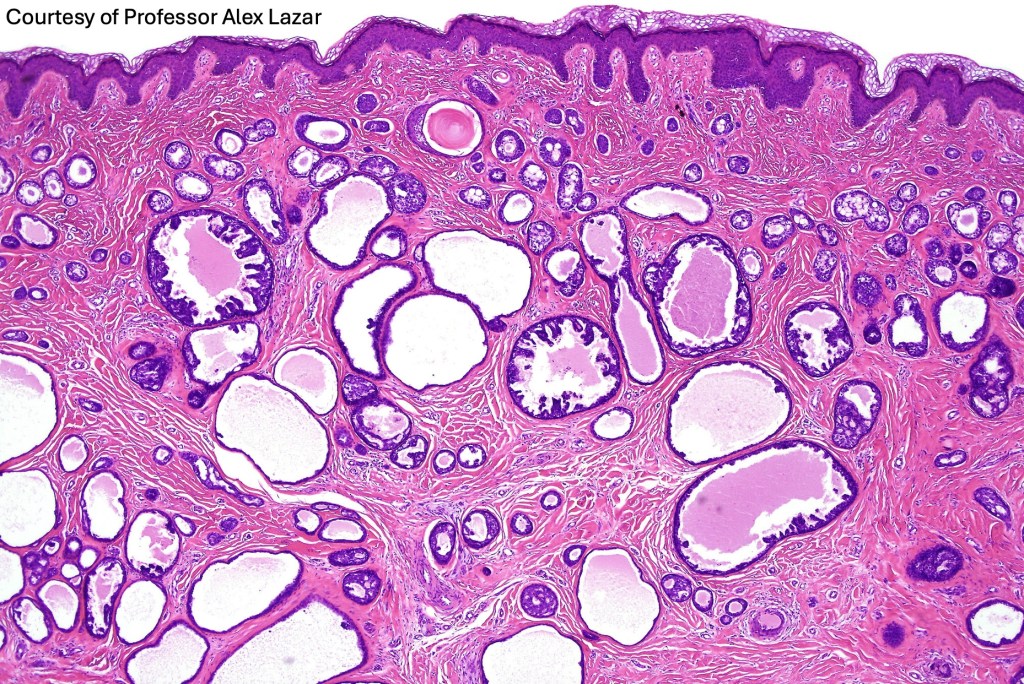

Histological features

•Circumscribed nodule composed of ducts & cysts embedded in a dense fibrous stroma sometimes associated with lymphoid aggregates/germinal centers

•Variable cribriform pattern